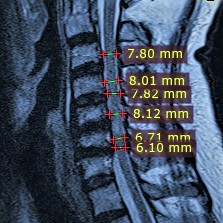

Cervical Spinal Canal Stenosis

Surgical Treatment